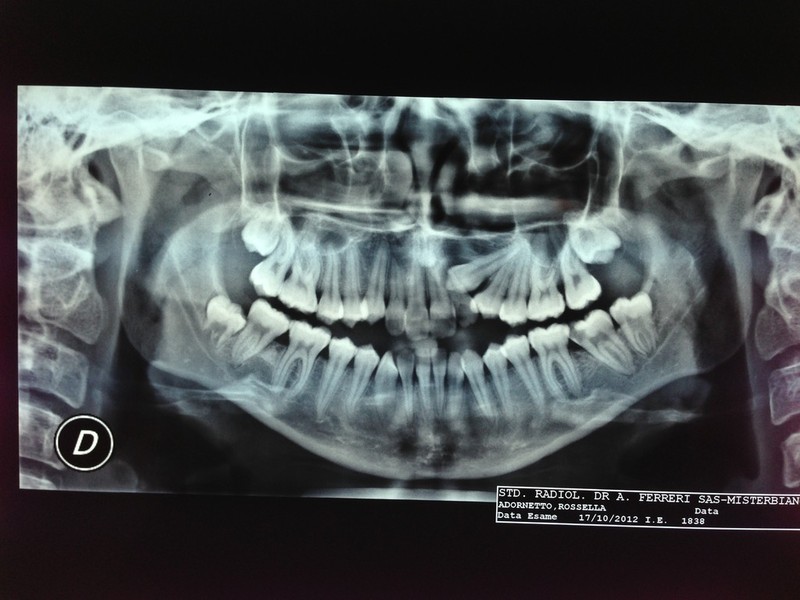

Paziente candidato a intervento di chirurgia Ortognatica